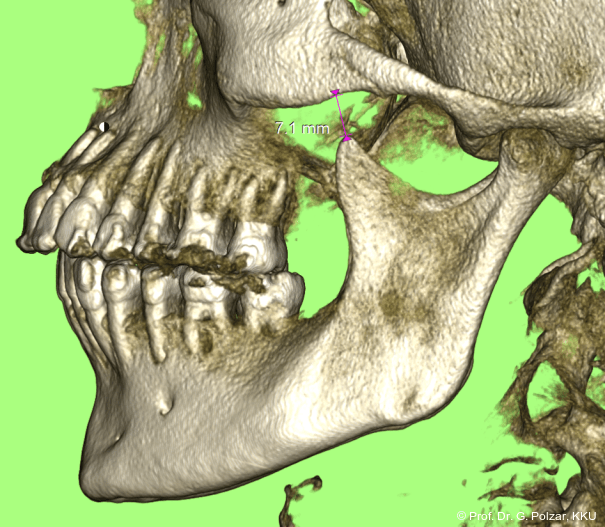

KG-Position: Die 3D-Ansicht im DVT zeigt eine vorverlagerte UK-Position bei neutraler Okklusion (Abb. 4a+b).

Im Sagittalschnitt zeigen beide Kiefergelenke eine deutlich anteriore Position. Der dorsokraniale Abstand betrug rechts 7,0 mm und links 5,8 mm. In der PEP waren sie im lateralen Bereich ca. 1 mm kleiner als in der Mitte der Sagittalprojektion (Abb. 6a–d).

Diese deutlich anteriore Gelenkposition im Neutralbiss ließ den Verdacht auf einen Sunday Bite zu. Das heißt, die Patientin schob den Unterkiefer aktiv nach vorne, um damit schönere Schneidezahnkontakte bzw. eine vermeintlich neutrale Okklusion zu erreichen. Nach mühsamen Lockerungsübungen gelang es der Patientin, auch in die zen­trale Kiefergelenkposition zu wechseln. So zeigte sich das ganze Ausmaß der Malokklusion. In neutraler KG-Position hatte die Patientin eine sagittale Frontzahnstufe von ca. 7 mm mit 1 PB Klasse II-Okklusion im Seitenzahn­bereich (Abb.5a+b, 7a–c).